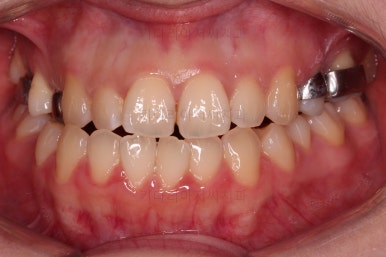

초진 시, 입안의 모습입니다.

아래 중앙선이 윗니의 정중선에 비해 우측으로 많이 쏠려있고요.

전반적으로 아래 치열이 우측으로 가 있어서 특히 송곳니 부분에서의 반대교합이 두드러졌어요.

(아래 송곳니가 위 송곳니보다 밖에 나와있는 상태)